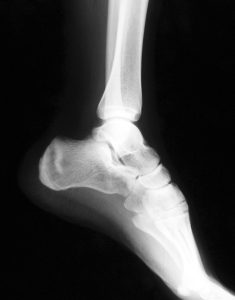

A fracture is a crack or a break within a bone. It can occur when force is applied against a bone, that is stronger than what it can structurally withstand. The most common bone fractures are those around the ankle, hip and wrist. Typically, fractures are treated with a plaster cast or by inserting metal rods surgically to hold the bone pieces together. Sometimes, however, complicated fractures may need surgical help. For the most part, treating broken bones is pretty routine for doctors. If your fracture is showing signs of healing, casts can be removed a few weeks after the injury had happened.